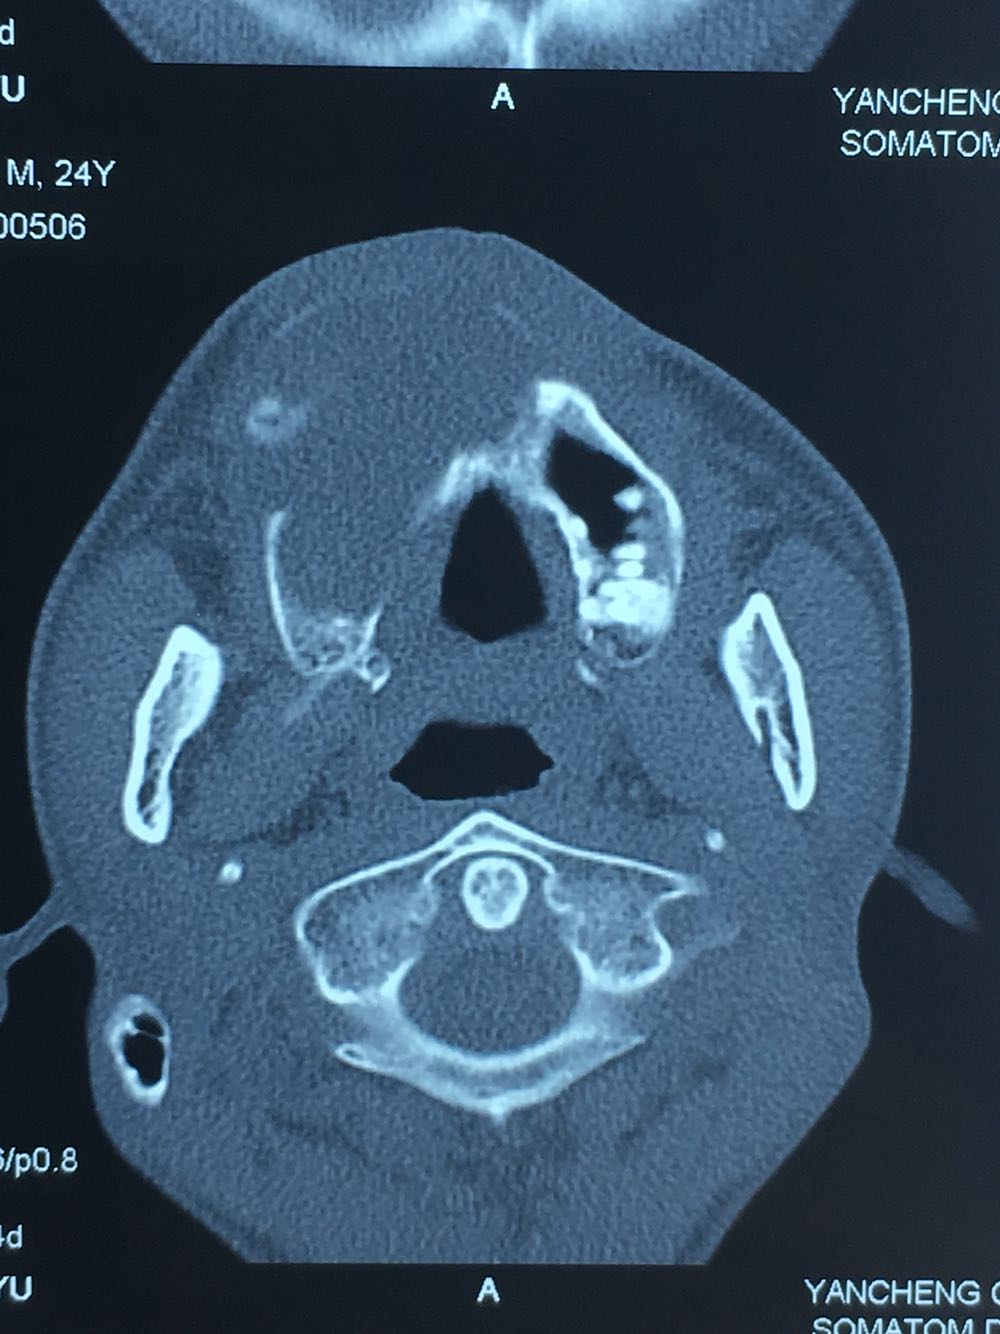

查体:面部明显不对称,右上颌膨隆明显,右鼻翼抬高,眶下区无麻木感,眼球运动自如,13牙齿缺如,16-22牙齿唇侧前庭肿胀,中央扪及波动感,边缘乒乓感,相关牙齿1度松动。 辅查:穿刺,抽得淡黄色液体,全景及CT,上颌骨囊肿,右侧上颌骨骨质大部分破坏

诊断:右上颌骨囊肿,13埋伏阻生。 治疗:开窗减压,拔除13阻生牙齿